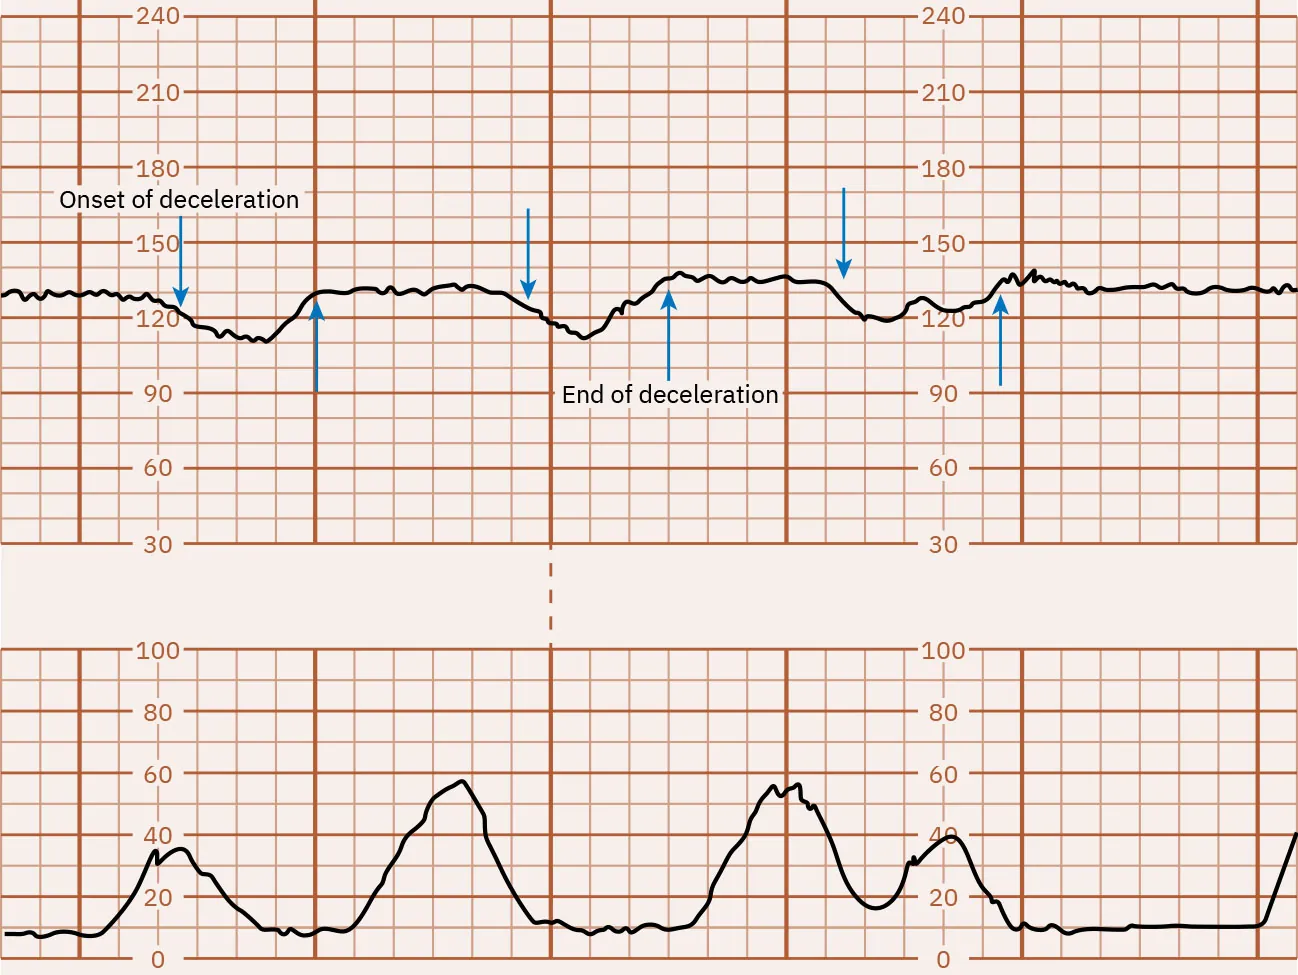

Early Decelerations

Gradual FHR declines that then return to baseline, mirroring the uterine contraction, are called early decelerations. Fetal head compression activates the vagal nerve, causing a deceleration in the FHR. The degree of deceleration is proportional to the strength of the uterine contraction. Decelerations are commonly seen during active labor as the fetal head descends into the pelvis. Early decelerations are considered normal. Figure 16.11 illustrates early FHR decelerations.

Fetal heart rate reading indicating early decelerations.

Figure 16.11 Monitor Tracing Showing Early Decelerations of the FHR These FHR decelerations are early because they mirror the uterine contraction. (attribution: Copyright Rice University, OpenStax, under CC BY 4.0 license)